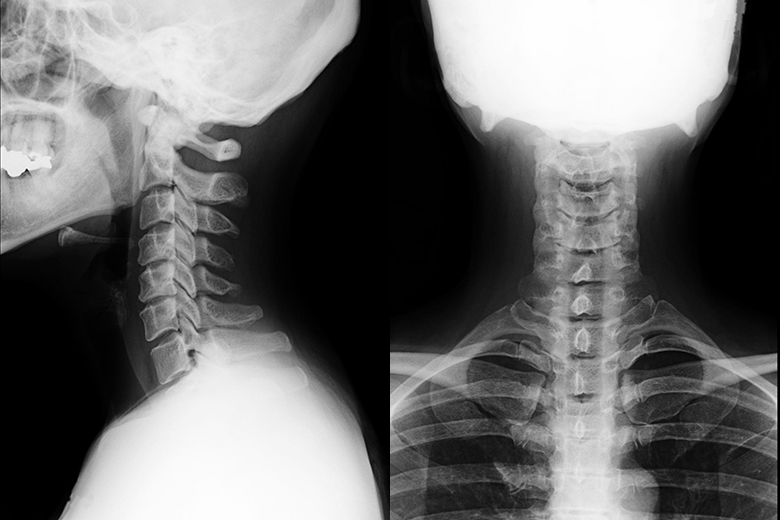

事故の直後は症状が出ないことも多く、病院の検査(レントゲンやMRI)でも異常が無いと言われることは少なくありません。

交通事故=病院というのが一般的ですが、なぜ事故後は病院を受診するのでしょうか?―それは、レントゲンやMRIなどの検査で、出血の有無や骨折・脱臼などの骨の異常を把握するためです。出血や骨折がないことを確認し、異常がないと判断されれば、鎮痛剤や湿布薬を処方され、痛みを抑えたり、痛みのある箇所を鎮静したりします。いわゆる、対処療法です。

病院で行うレントゲンやMRIなどの画像診断は、出血や骨折の有無を把握することができますが、実は筋肉や神経の異常を把握することはできないのです。そのために、筋肉や神経が原因で起こっている痛みにも対処療法が施されるため、痛みを根本から改善することが困難となります。その病院でも治療することが難しい、筋肉や神経の異常にアプローチできるのが、整骨院です。